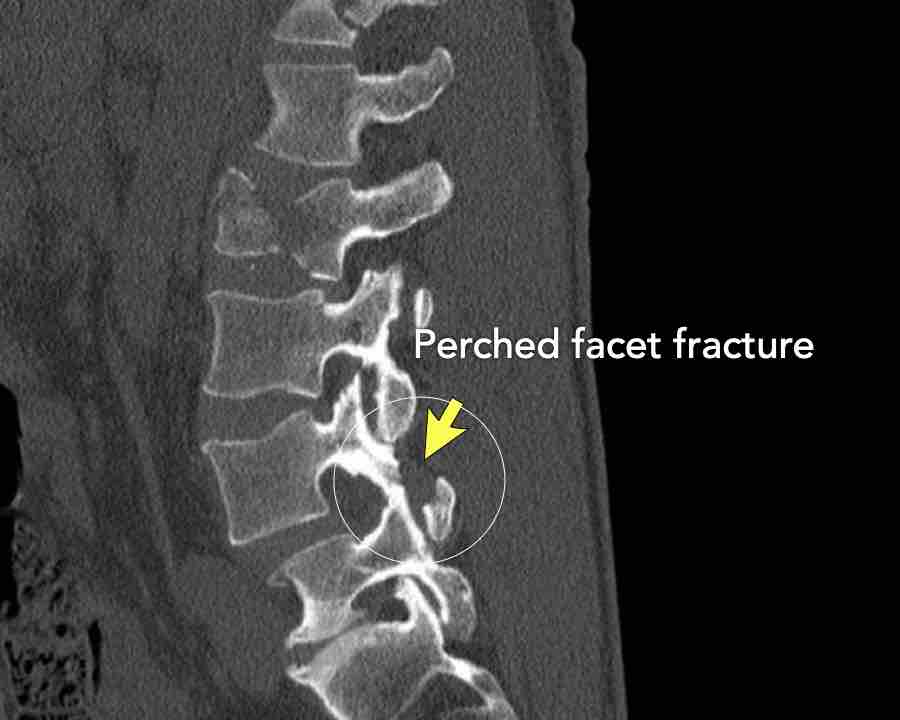

Scroll through the images

Findings:

- Perched facet joints (yellow curved arrows), so think of C injury.

- Posterior displacement of the vertebral bodies in the midline.

- Secondary A4 injury of the vertebral body.

Conclusion

Type C + A4 injury